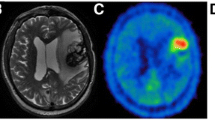

Among the 17 of 24 patients who ultimately presented with tumour progression, ten experienced tumour recurrence and seven, regrowth of residual tumour. These diagnoses were histopathologically proven by stereotactic biopsy in five patients and by re-operation in three patients. In the remaining nine patients, suspected tumour regrowth or recurrence was assumed because of concordantly increasing contrast enhancement on MRI and clinical deterioration. Table 2 summarises the characteristics and results of patients with progressive disease. The ten patients without obvious tumour at baseline initially presented with normal ratios (TUmax/BG 1.64±0.26) but showed focally increasing FET uptake values, resulting in pathological ratios during follow-up (TUmax/BG 2.67±0.43). A representative example is shown in Fig. 2. In seven patients with known residual tumour on the baseline scan, further FET PET investigations demonstrated pathological ratios which were stable or increased over time (baseline TUmax/BG 2.49±0.42; last follow-up TUmax/BG 3.04±0.49). Six of these seven patients showed pathological contrast enhancement on baseline MRI as well. Most interestingly, in one of the seven patients (with anaplastic astrocytoma WHO grade III), MRI was rated as normal owing to the lack of contrast enhancement, whereas the concomitant PET scan showed pathological focal FET uptake ventral of the cavity, clearly indicating recurrence. This was proven by stereotactic biopsy. This patient underwent re-operation of this area, but unfortunately developed another tumour manifestation distant from the primary location that showed contrast enhancement on MRI as well (Fig. 3).

Serial MRI and FET PET images of a 69-year-old man after surgery and radiation therapy of a glioblastoma located in the left occipital lobe during and after two RIT cycles (07/04 and 10/04 with 470 MBq 188Re-TN-mAb). Slightly increased homogeneous FET uptake is evident surrounding the tumour cavity (07/04–12/04). Development of tumour recurrence lateral to the resection cavity is indicated by additional nodular FET uptake as shown in the last scan (03/05). The respective TUmax/BG ratios are given below the PET images

Serial MRI and FET PET scans of a 30-year-old man after surgery and radiation therapy of an anaplastic astrocytoma WHO III located in the right parietal lobe before and after 1 RIT cycle (07/02 with 1870 MBq 131I-TN-mAk). a At baseline and 3 months after therapy, slightly increased homogeneous FET uptake at the cavity borders with additional nodular FET uptake ventral of the cavity indicating recurrence. MRI shows no suspicious contrast enhancement. b After reoperation development of another tumour manifestation developed distant the primary location with focal FET uptake and contrast enhancement on MRI as well. The respective TUmax/BG ratios are given below the PET images